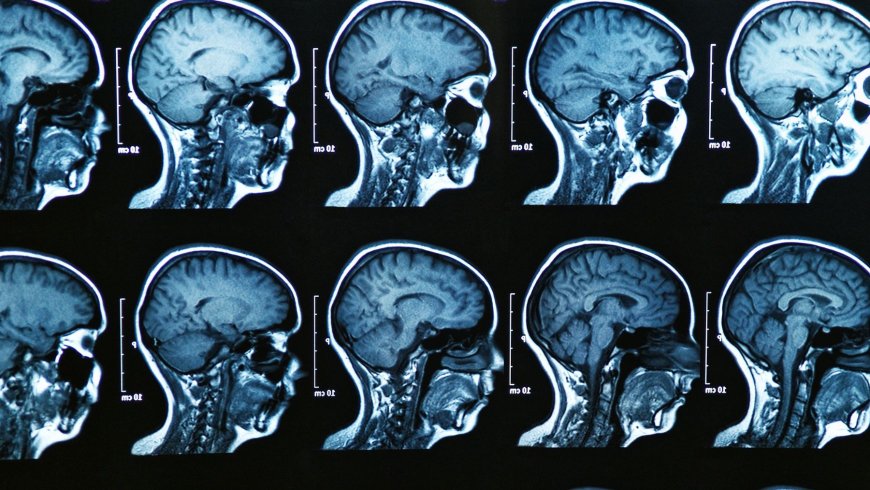

From the outside, a 19-year-old and a 30-year-old may not look very different. But brain scans tell another story. Using MRI technology, researchers began tracking how different regions of the brain change over time.

They found that certain areas were still reorganizing long after high school. Connections between brain cells were being strengthened, removed, and rebuilt. The brain was refining itself, almost like editing a draft.